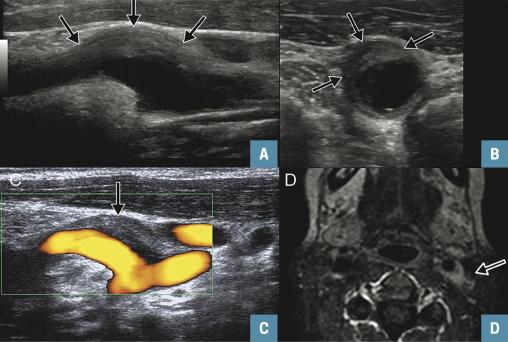

Un échodoppler des troncs supra-aortiques (TSA) est réalisé pour éliminer une dissection carotidienne. Il montre, au niveau du bulbe carotidien gauche, une lésion pariétale, algique à la pression, responsable d’une sténose non significative (fig. 1A à 1D ).

Un échodoppler des troncs supra-aortiques (TSA) est réalisé pour éliminer une dissection carotidienne. Il montre, au niveau du bulbe carotidien gauche, une lésion pariétale, algique à la pression, responsable d’une sténose non significative (

Une IRM cérébrale et cervicale avec injection est réalisée. Elle met en évidence, à l’étage cervical, un épaississement excentré marqué, en isosignal T1 et hétérogène en T2. Une prise de contraste périphérique de la bifurcation carotidienne gauche est également constatée. L’ensemble est évocateur d’un TIPIC syndrome (fig. 2 ).

Une IRM cérébrale et cervicale avec injection est réalisée. Elle met en évidence, à l’étage cervical, un épaississement excentré marqué, en isosignal T1 et hétérogène en T2. Une prise de contraste périphérique de la bifurcation carotidienne gauche est également constatée. L’ensemble est évocateur d’un TIPIC syndrome (